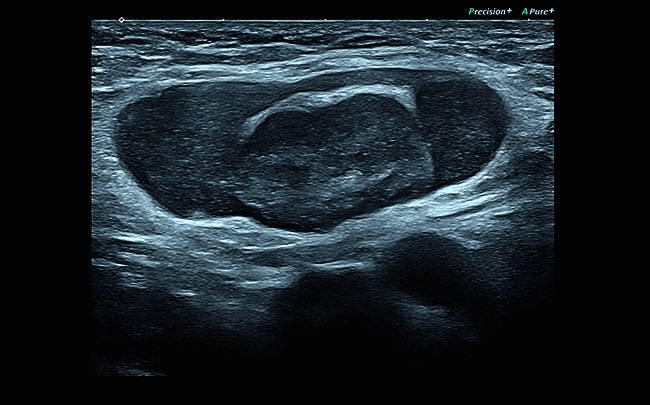

Компрессионная эластография

Эта методика выявления опухоли, построенная на анализе отличий модулей продольной упругости, была принята в качестве общего стандарта и применяется для детального исследования поверхностно расположенных органов. С ее помощью вы сможете добиться детального и по-настоящему качественного результата проводимого исследования.

Компрессионная эластография:

Да